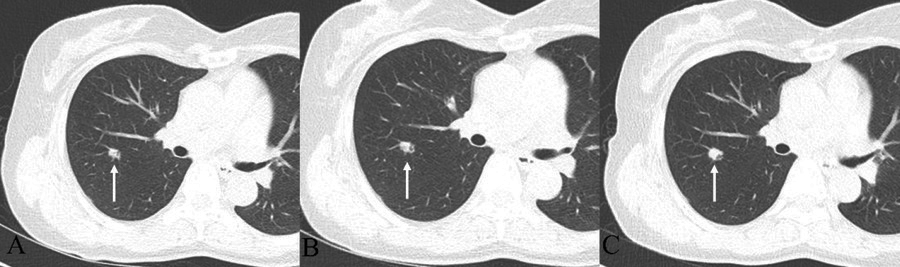

A 60-year-old woman presented to the pulmonologist with a 9-mm solitary lobulated nodule in the right upper lobe as an incidental finding on screening chest radiography (Figure 1) and chest computed tomography (CT) (Figure 2A). All laboratory results were within normal limits. Follow-up CTs showed an increase in nodule size, from 9 mm initially to 10 mm after a year and 13 mm at the 2-year follow-up. The total volume doubling time (VDT) from the initial to the 2-year follow-up was 369.45 days, indicating a potential malignancy with a value below 400 days (Figure 3) [5]. Furthermore, air bronchograms became more evident and dilated, a feature known to be worrisome (Figure 2B, C). This growth and development of the air bronchogram suggest lung malignancy.

Figure 2

Chest CT with follow up. (A) 9-mm lobulated nodule with an internal air-bronchogram in the right upper lobe. (B) After 1 year, the nodule shows a minimal increase in size, 9 to 10 mm. (C) After 2 years later from the initial chest CT, the nodule changes from 10 to 13 mm in size, and the somewhat dilated internal bronchus are detected.

Figure 3

Volume: After 1 year, the volume doubling time from the initial state was 844.28 days, and the overall average volume doubling time after 2 years was 369.45 days.